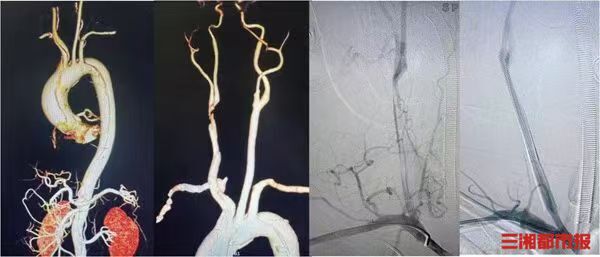

一颗小小的钢珠,从玩具射钉枪中意外射出,竟从男童的下巴直穿颅内,引发严重感染、脑脓肿,患儿生命危在旦夕。记者今日从湖南省儿童医院获悉,该院神经外科凭借多学科协作的科学诊疗思路,结合先进的机器人导航技术,成功为这名危重患儿实施高难度手术,精准取出颅内钢珠、清除脓肿,成功化解这场罕见的颅脑创伤危机。